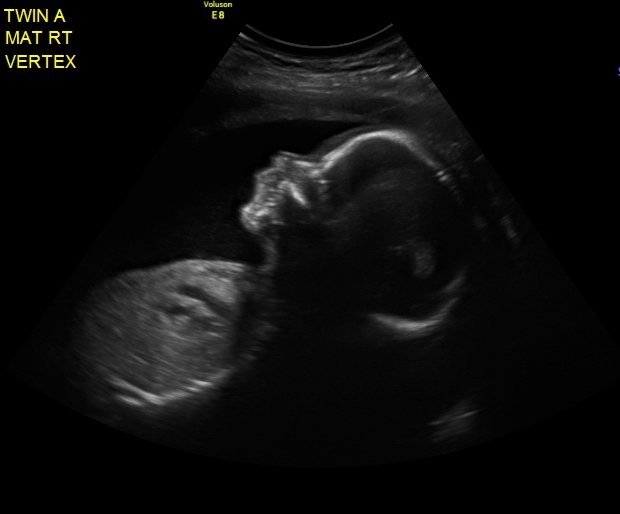

Updates? We had our first BPP done last week @ 32w1d - and both babies looked great - but the most exciting part was that Baby B (who has been breech since around 20 weeks) FLIPPED and now both are head down!!!!!! Looking back I know when it happened - and it was around 30w or so. But now my chances of a vaginal delivery are so much better! Although now I am worried that she is going to flip back - but I keep telling myself they are running out of room in there. Both babies were estimated at over 4lbs each too! It's so crazy.